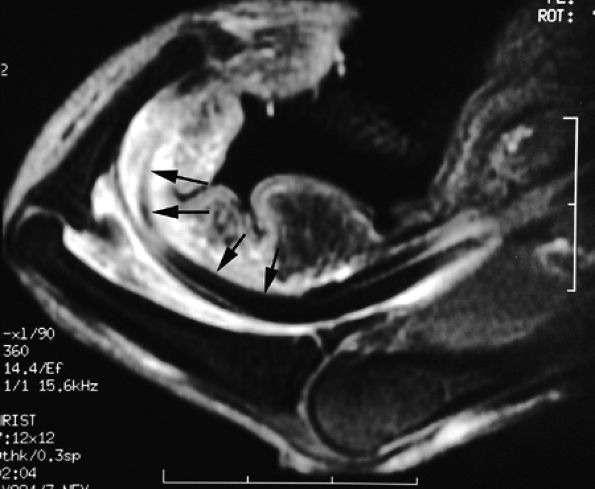

FIGURE 11.60 ● Posttraumatic arteriovenous fistulas. Axial post-contrast 3D gradient-echo image shows peripheral enhancement (arrows) and a central flow void (asterisk) due to high velocity.

|